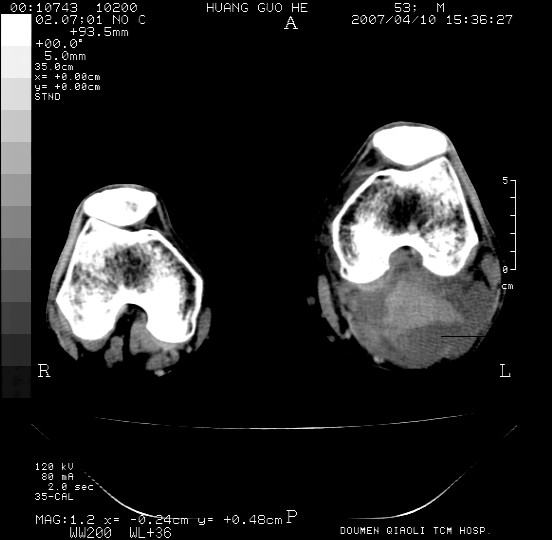

男性,左腘窝包块五个月,逐渐增大,疼痛功能受限,无发热。

查:远端血供差,质地硬。

左侧膝关节后国窝处略低密度软组织肿块,边界清楚,内见脂肪密度及高密度影.多考虑:软组织肿瘤_首选:脂肪纤维瘤.

左侧腘窝软组织肿块,边缘清晰,其内密度不均,周围骨组织无破坏,病灶增长较快,考虑:恶性病变(腘窝滑膜肉瘤可能),建议穿刺活检。